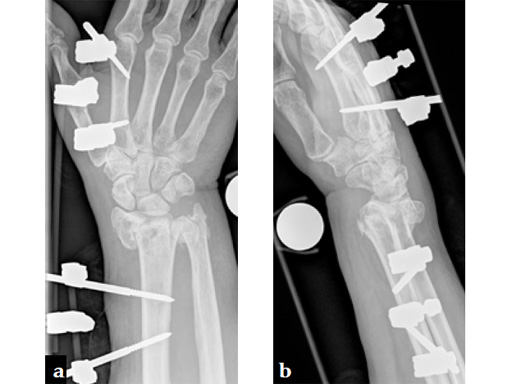

Fig 5ab Six weeks postoperatively: residual swelling, little pain, range of motion improving with physiotherapy; the patient uses her hand for daily activities.